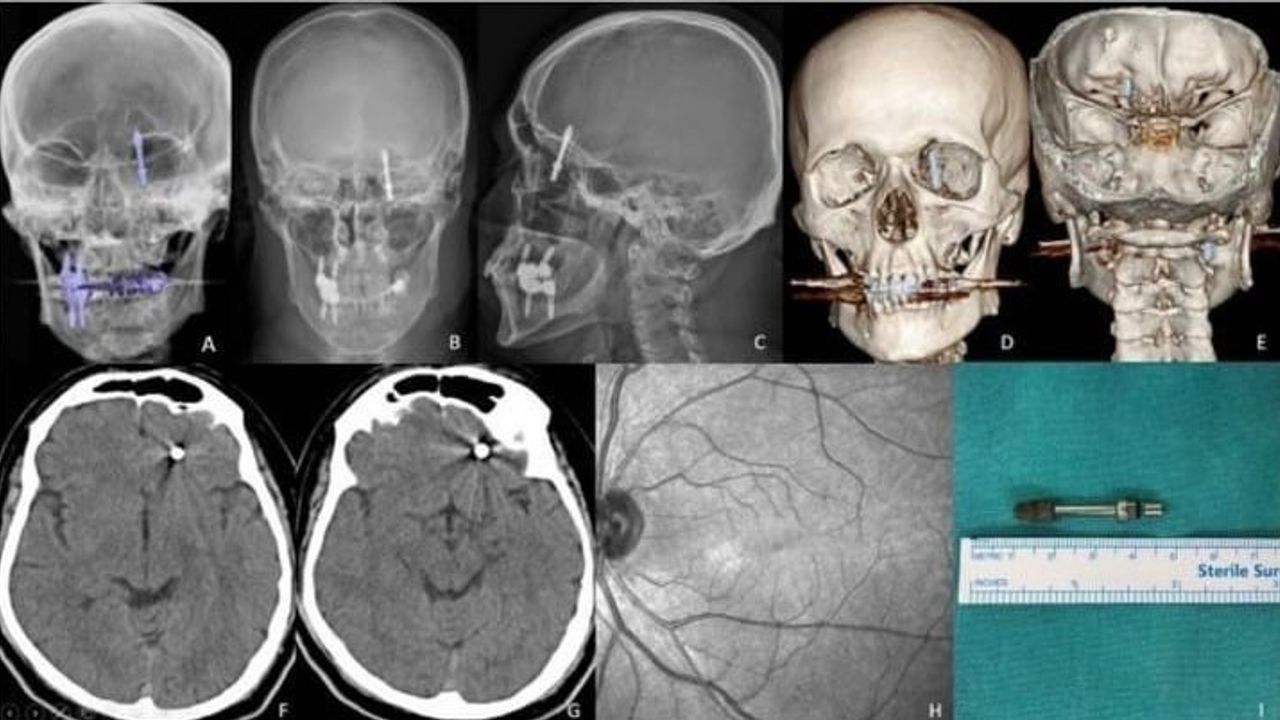

Nilüfer ilçesinde özel bir diş kliniğinde muayene olan Yılmaz'a, dişlerinin sallandığı gerekçesiyle implant tedavisi önerildi. Ancak iddiaya göre, doktor A.D.'nin hatalı müdahalesi sonucu implant vidası çene kemiğini delip kafatasına saplandı.

Baygınlık geçiren Yılmaz, kliniğin kendi aracıyla hastaneye kaldırıldı. Tomografi çekiminde vidanın beynine kadar ilerlediği ortaya çıktı. Acil ameliyata alınan talihsiz adam, saatler süren operasyonla ölümden döndü.